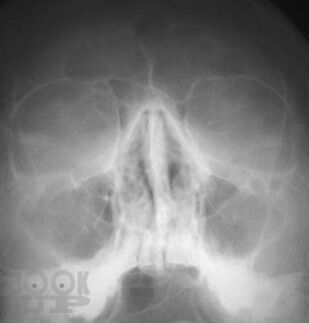

Рентгенографическая и компьютерно-томографическая диагностика острых и хронических синуситов

Монография посвящена применению классической рентгенографии и рентгеновской компьютерной томографии для диагностики острых и хронических воспалительных заболеваний околоносовых пазух. Результаты обоих исследований сопоставлены между собой по разработанной авторами методике, предложены адаптированные к практической работе подходы к обоснованному выбору указанных методов рентгенодиагностики синуситов. Книга хорошо иллюстрирована, содержит примеры описания рентгенограмм и компьютерных томограмм околоносовых пазух.

Книга рассчитана на врачей-рентгенологов, в том числе работающих на рентгеновских компьютерных томографах, врачей-оториноларингологов, интернов и ординаторов кафедр лучевой диагностики.